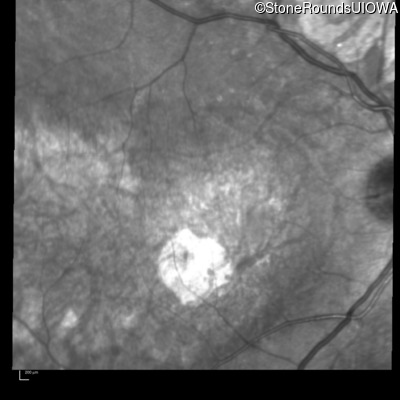

Infrared Fundus Photograph - Right - 20/100

Exemplar

Infrared Fundus Photograph - Left - 20/100